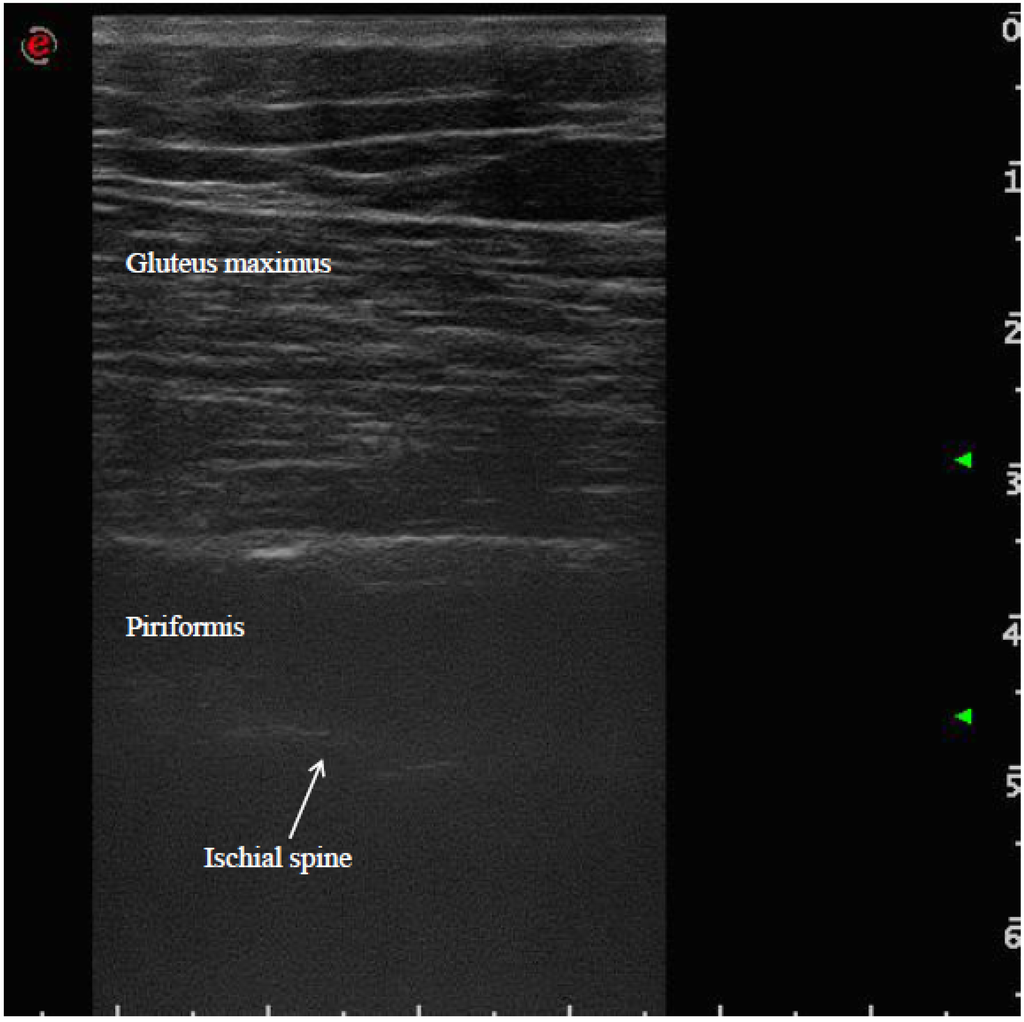

Ultrasound-Guided Injection of Botulinum Toxin Type A for Piriformis Muscle Syndrome: A Case Report and Review of the Literature

2. Methods